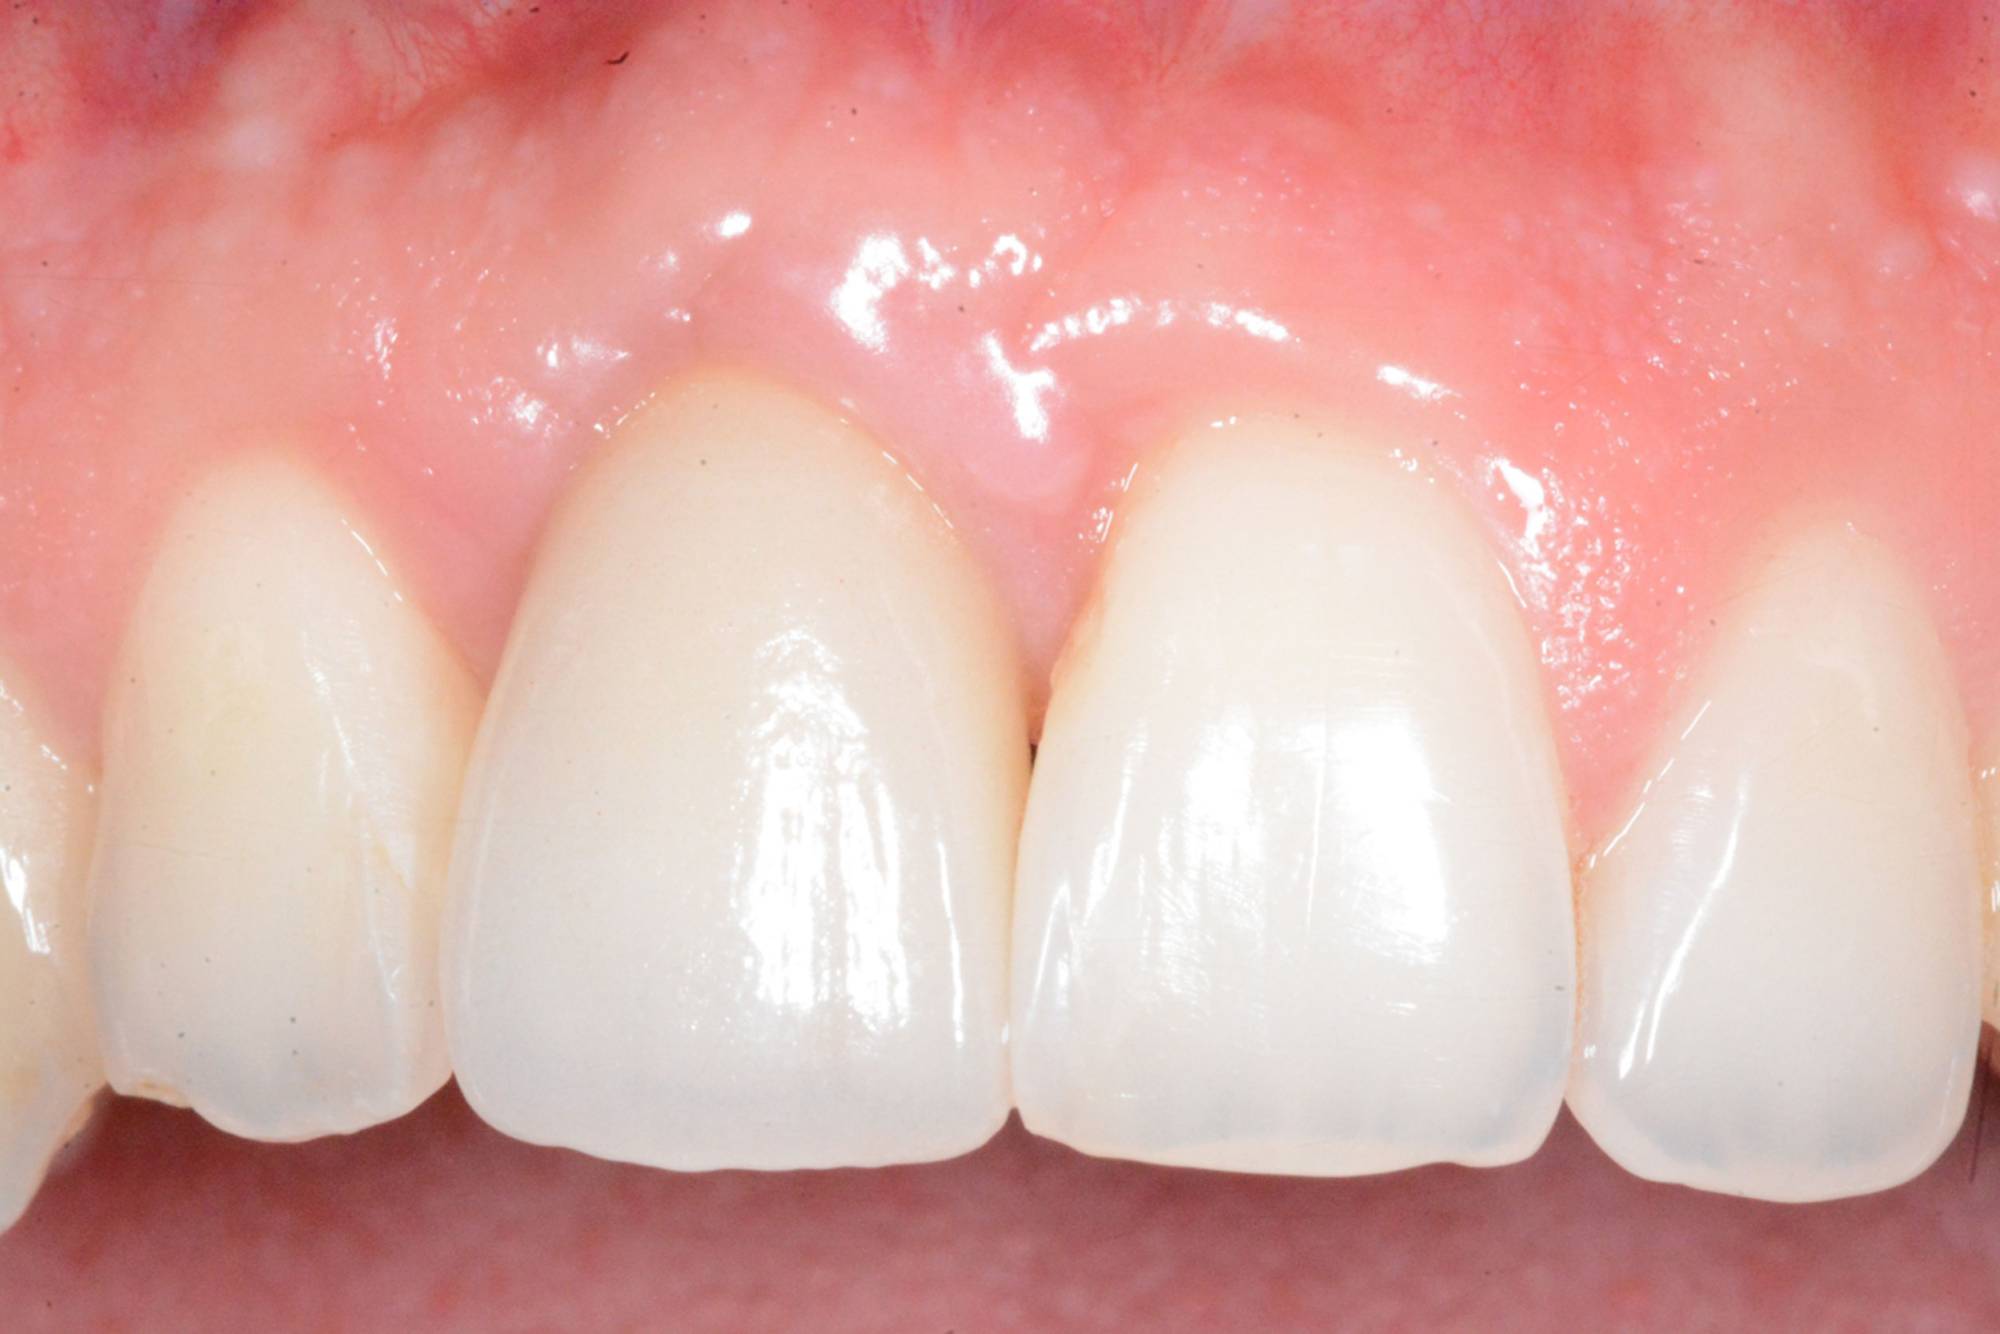

L'impianto dentale osteointegrato è una sorta di radice artificiale che si inserisce nell’osso del paziente, per rimpiazzare un dente mancante.

L'impianto, oltre a essere un metodo sicuro, garantisce l'aspetto esteriore e la piena funzionalità di un dente naturale. Oltre a ciò, mantiene l’integrità dell’osso, non va ad intaccare i denti adiacenti - come invece farebbe un ponte - e migliora l’estetica facciale prevenendo la perdita ossea.

In questo lasso di tempo, nel quale l'impianto è sommerso sotto la gengiva e si avvia il processo di guarigione ossea, si realizza l'osteointegrazione, ovvero un intimo contatto fra l’osso e la superficie biocompatibile in titanio dell’impianto.